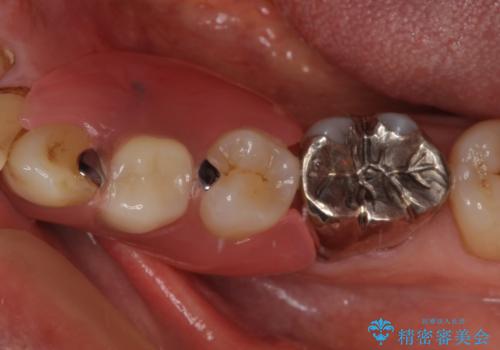

- 近医にて抜歯が必要と言われたとのことで来院された患者様です。

顕微鏡下で確認したところ、歯根に及ぶ破折線が認められたため、抜歯を行うこととしました。

インプラント治療をお勧めしましたが、取り扱いや手入れが煩雑でも良いとのことで、可撤性義歯(入れ歯)にて補綴治療を行うこととしました。